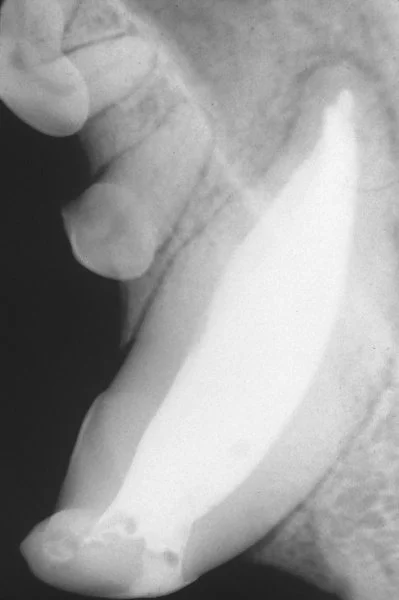

마취가 된 후에는 구강상태를 평가하고, 치열, 치석 및 플라그에 대해 평가합니다. 치아 방사선을 촬영을 통한 치아 뿌리 및 주변 뼈들에 대한 상태를 볼 수도 있습니다. 만약에 치주질환이 매우 심하다면, 치아를 살리는 게 불가능할 수도 있는데, 이 경우 치아를 발치합니다. 이후에 스케일링이 시작되는데, 스케일링을 통해서 잇몸 라인의 위아래로 스케일리을 하게 됩니다. 잇몸 안쪽의 치석은 매우 심각한 잇몸 손실을 유발할 수 있기 때문에, 가장 중요하게 제거됩니다. 스케일링 이후에, 폴리싱을 통해, 아주 미세한 상처들을 마모하는데, 이런 상처들에 이차적인 플라그가 형성되기 쉽기 때문입니다. 그 외 플루오이드나, 항생제, 그리고 세정제등을 이용해서 치아의 민감도를 낮추고, 에나멜질을 강하게 하고, 세균을 컨트롤합니다. 그리고 미래의 플라그 축적을 감소시킵니다.

Once your dog is anesthetized, your veterinarian will thoroughly examine the mouth, noting the alignment of the teeth and the extent of tartar accumulation both above and below the gumline. Your veterinarian may also wish to perform dental radiographs to assess the viability of the tooth root and surrounding bone. If periodontal disease is severe, it may not be possible to save badly affected teeth, which may need to be extracted. Next, tooth scaling will be performed using both traditional hand scalers and ultrasonic cleaning equipment to remove all traces of tartar, both above and below the gum line. The tartar below the gum line causes the most significant gum recession and it is extremely important that it is removed thoroughly.